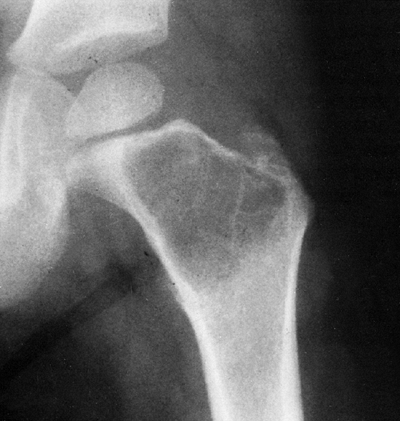

diagnostic. The typical lesion is located in the metaphysis, involves

pattern) (Figs. 14.7 and 14.8).

![]() |

Figure 14.7

Anteroposterior plain radiograph of an 18-year-old man with an osteosarcoma of his proximal tibia. There is increased density in the proximal tibia associated with cortical destruction and extraosseous bone formation. Biopsy was confirmatory. |